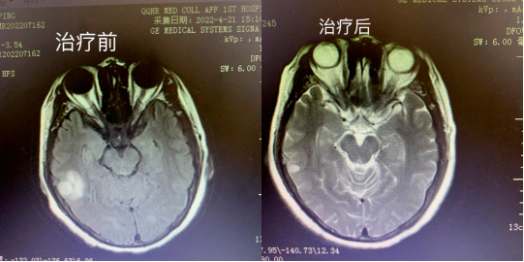

治疗前后对比

我们可以看到,该患者满肺的转移病灶几乎清除殆尽,脑转移病灶缩小明显,大部分已经消失。